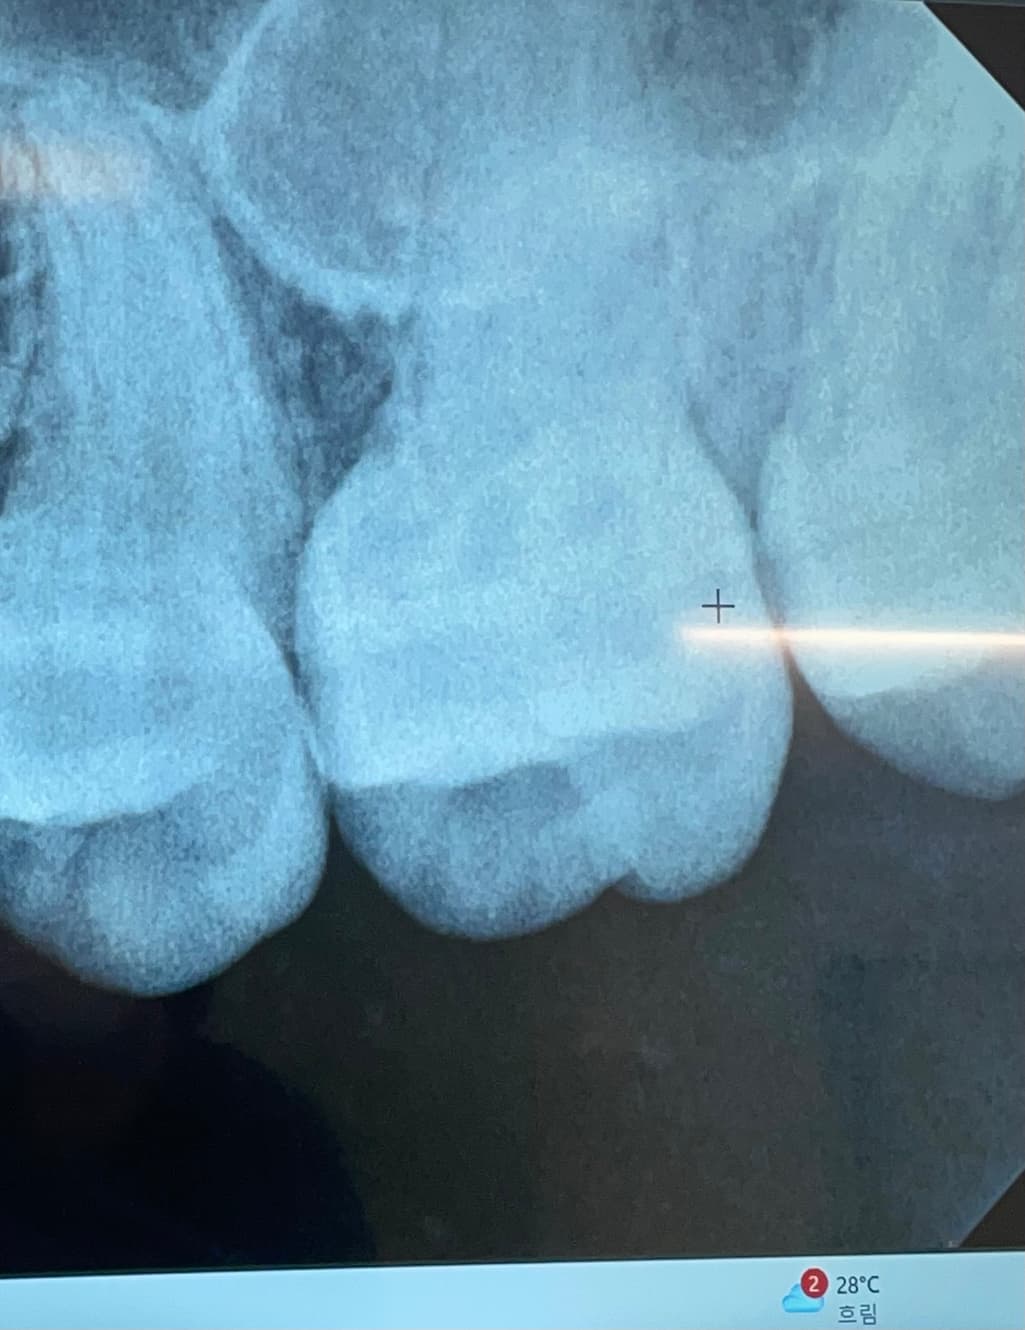

치과에서 따로 언급은 안하셨는데 사진의 치아 사이도 충치 있는 건가요..? 충치 없어도 엑스레이 상에는 원래 저런건가요?…….

엑스레이 상으로는 치아 사이에 충치가 없어도 촬영각도나 치아에 따라서 충치치럼 보이는 경우도 있습니다.

사진만으로 판별하기에는 어려움이 있지만 심하진 않고 초기 우식 정도는 가능성이 있어보입니다.

사진으로 봤을 경우 방사선으로 약간 음영에 보이긴 합니다. 하지만 충치가 있다고 확신을 할 순 없으며 육안상 확인이 필요할 것으로 생각됩니다.

자세한 확인을 위해서 치과에서 진료를 받아보는 것을 권유드립니다.